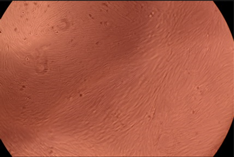

| Sample | Micrographs | ||

|---|---|---|---|

| 24 h | 48 h | ||

| Control |  |  | |

| F127 | 10 µg/mL |  |  |

| 50 µg/mL |  |  | |

| 100 µg/mL |  |  | |

| 200 µg/mL |  |  | |

| F127/PA = 10/1 (g/g) | 10 µg/mL |  |  |

| 50 µg/mL |  |  | |

| 100 µg/mL |  |  | |

| 200 µg/mL |  |  | |